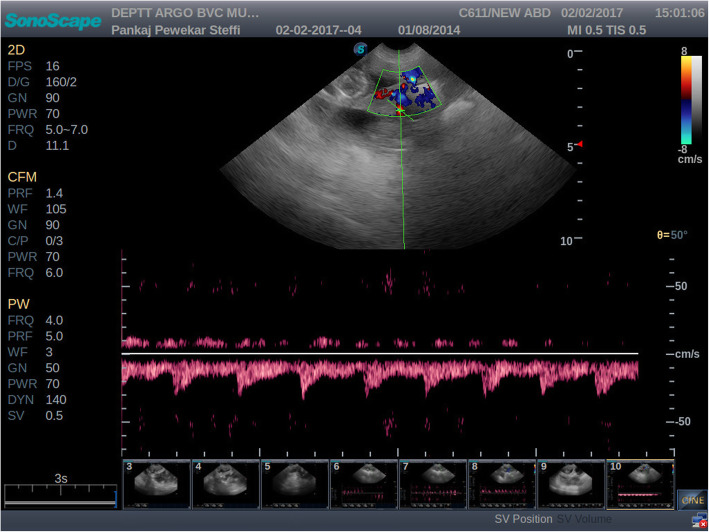

All the experimental bitches were subjected to ultrasound examination during 40 to 50 and 51 to 60 days of gestation. Colour and pulse wave Doppler ultrasound examination of the uteroplacental vessels and umbilical arteries was performed. Compared to velocimetry of arcuate arteries, Doppler sonography of the uterine arteries in human permits a more general evaluation of uterine perfusion. In humans the vaginal route is preferred to trans-abdominal scanning as it has shown to eliminate errors due to its proximity to the uterine vessels [17]. This approach however, is not possible in bitches without sedation. Also, it is difficult to locate the uterine arteries trans-abdominally in advanced gestation [17]. Hence, in the present study, the uteroplacental arteries were studied rather than the uterine arteries. Utero-placental arteries were scanned either adjacent to the gestational sac or between two gestational sacs. Blood flow was detected by imaging the area mentioned and applying colour Doppler mode of the ultrasonography machine. Once the blood flow was detected, a pulsed-wave Doppler was performed to obtain the waveform of the uteroplacental arteries [Fig. 1 and Fig. 2]. The Doppler waveform obtained on pulsed wave evaluation was frozen and the values for SPV, EDV were obtained by manually tracing three consecutive waveforms. The PI and RI were obtained automatically from the machine itself.

Fig. 1.

Pulsed wave Doppler image of uteroplacental arteries during 40 to 50 days of gestation in threatened abortion cases. The wave form of the uteroplacental arteries in the threatened abortion cases was quite different than the normal gestation. It was observed that during 40–50 days a systolic peak was followed by full diastole, with broadening and progressive flattening of the diastolic upstroke. This culminated in a monophasic wave with little oscillation during diastole. This wave morphology might suggest vascular pathology due to the placentitis